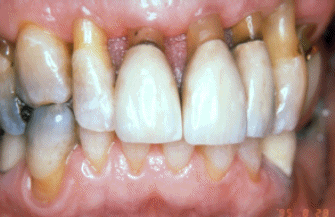

Mujer de 68 años de edad tratada por enfermedad periodontal por medio no quirúrgico (raspado y alisado radicular) seis años antes. El margen  gingival se ha retraído entre 3-5 mm y las profundidades de los surcos al sondaje es de  2 - 3 mm. Ella demuestra una higiene oral excelente y la progresión de la  enfermedad periodontal se ha detenido. Se observa signos de abrasión dental por el cepillado en los incisivos.

Mujer de 68 años de edad  que fue tratada por medio de tratamiento no quirúrgico (raspado y alisado radicular) hace ocho años. El margen  gingival se ha retraído entre 3-5 mm. Las profundidades de los surcos gingivales son 2-3 mm. Ella demuestra una higiene oral excelente y la progresión de enfermedad periodontal se ha detenido. Se observa evidencia de abrasión por el cepilldo dental. a lo largo del margen gingival.

Esta imagen demuestra la condición después de 10 años. Las coronas anteriores se han rehecho. El paciente tiene una línea de la sonrisa baja y las líneas de preparación supragingival no perturban su estética. Ella ha mantenido un excelente control de placa bacteriana y no se obseva signos de enfermedad periodontal. La abrasión ocasionada por el cepillado dental ha aumentado. Ella acostumbra usar un cepillo suave y pasta dental no abrasiva para reducir el desgaste dental por el cepillado diario.